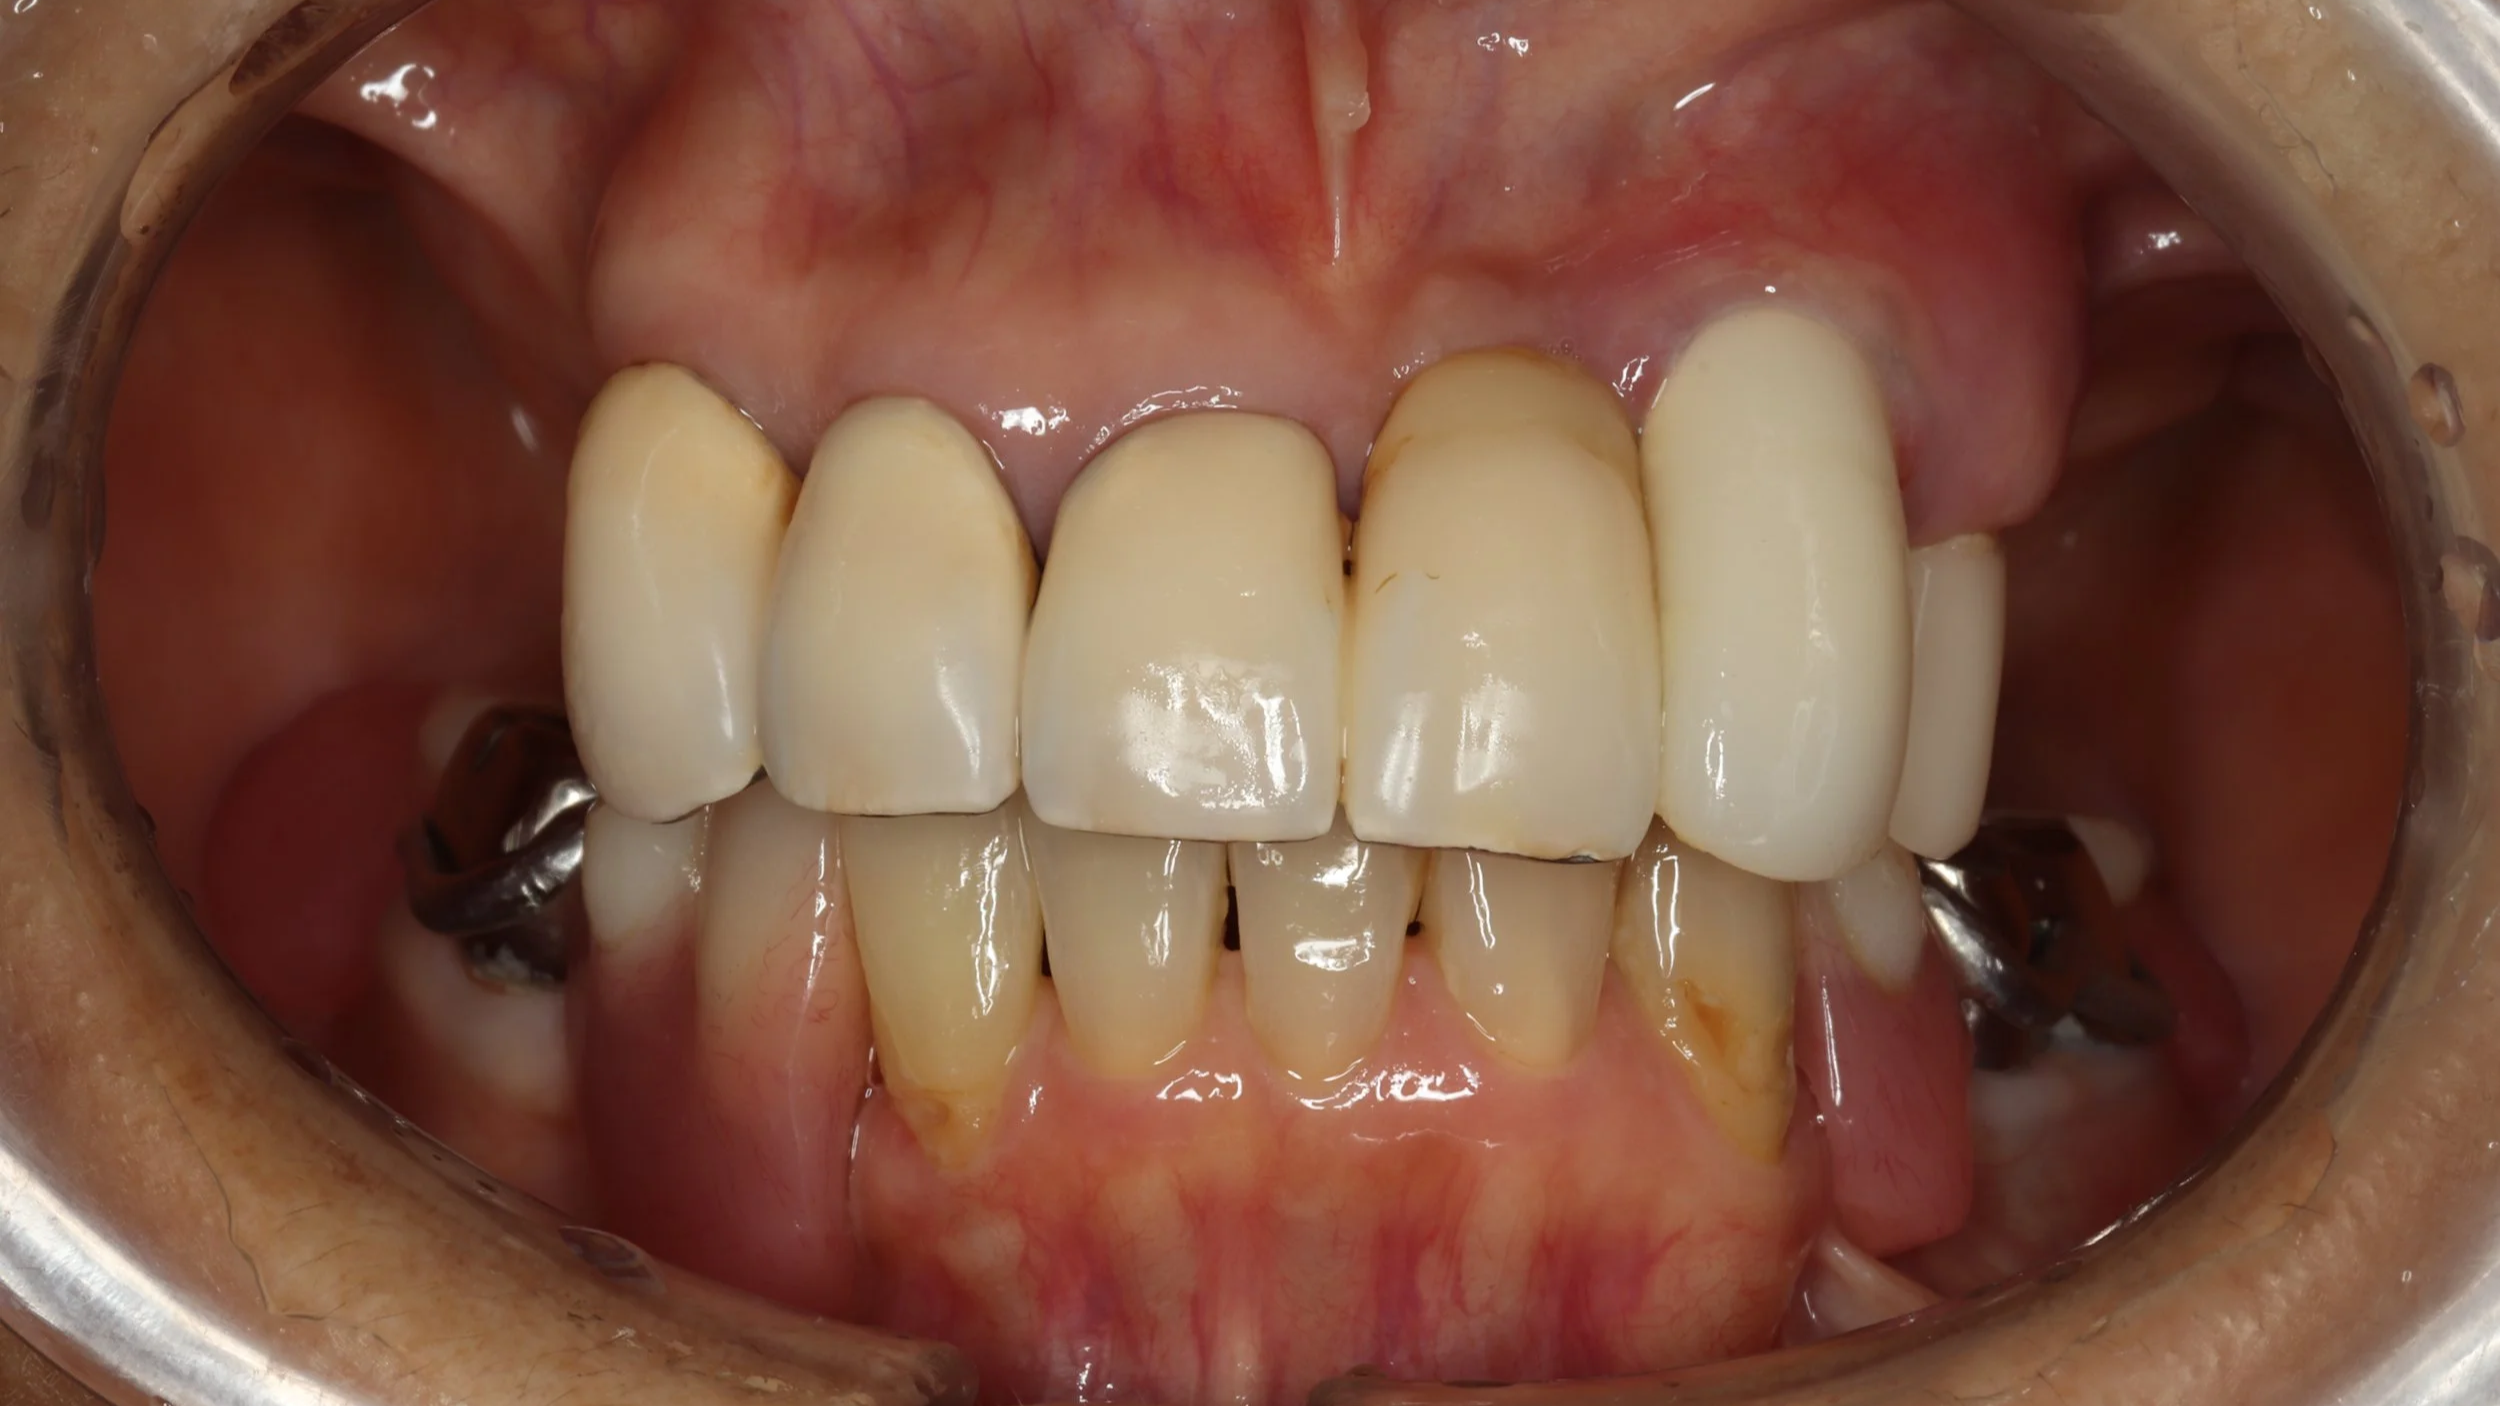

今回はできるだけ薄く作りたいという希望もあったことから、金属床を用い製作、前歯の抜歯とともに同日に新しい入れ歯を装着。

デジタルデンチャー

奥の歯には、金属で入れ歯を止めるバネを製作し、前歯の見える部分には、透明なレジンクラスプを使用しました。